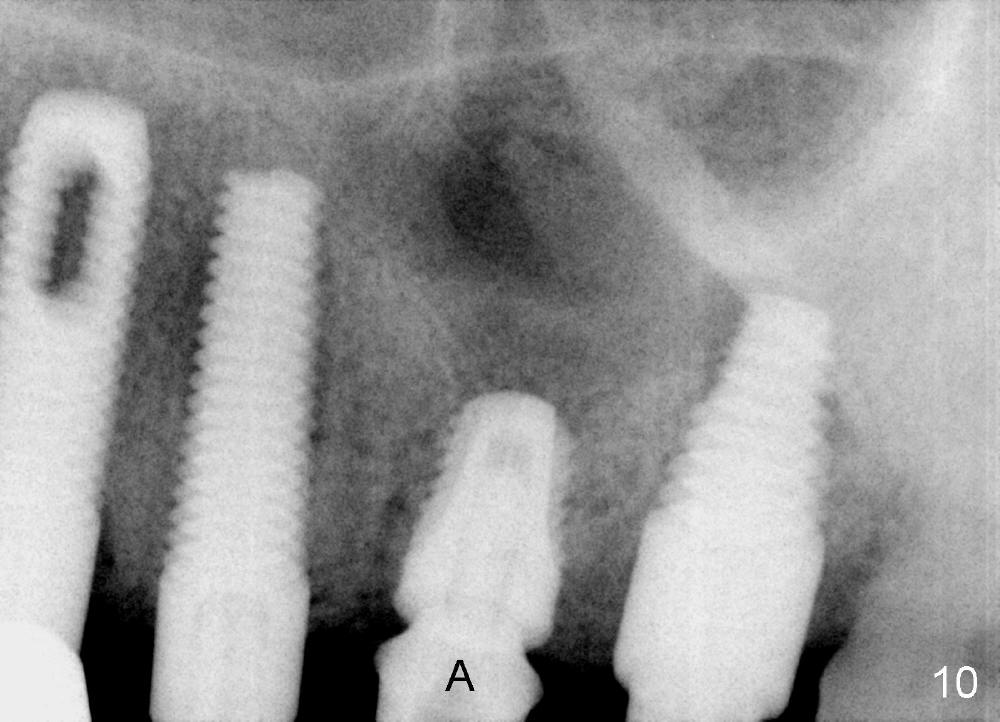

The provisional dislodges once more several days later.  The implant at the site of #14 is uncovered; an abutment (A) is placed (Fig.10.11); a provisional (Fig.12 P) 3-unit bridge is fabricated and cemented securely.  There is some occlusal contact with the opposing teeth.